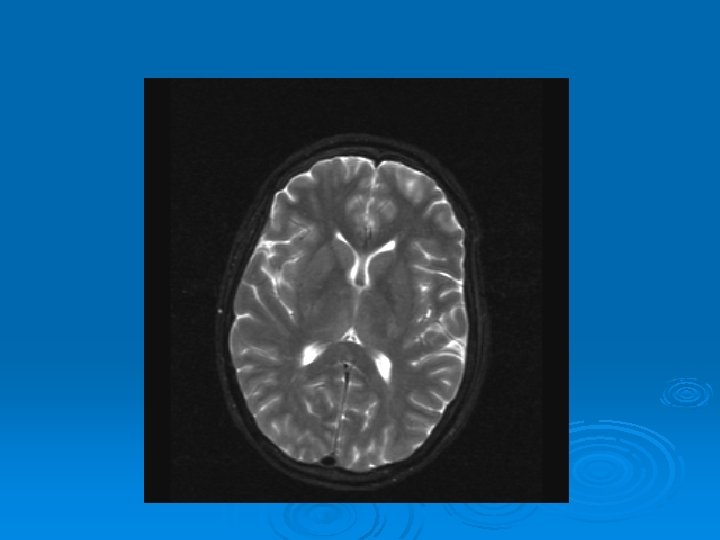

MRI: 2/9/2007 Ø 1. Leptomeningeal enhancement, most prominently seen over the posterior parietal and occipital lobes.

CMV: Ventriculoencephalitis Ø Clinical: Can have abrupt presentation of confusion, apathy, impaired memory, withdrawal, nystagmus, motor weakness, cranial nerve deficits, ataxia, seizures, coma. Can rapidly progress. Ø Labs: CSF: Monocytic Pleocytosis, Low Glucose CMV PCR Positive in CSF: (Sensitivity, Specifity 80, 90%, PPV, NPV, 86 -92, 9598%) Serum CMV viremia Ø Ø Ø MRI: Subependymal enhancement, diffuse hyperintense T 2 WI, ventriculomegaly.

MRI of CMV patient Magnetic resonance images of a patient with cytomegalovirus ventriculitis Ependymal enhancement after injection of gadolinium. DPTA seen on coronal T 1 -weighted image. Ø Highly abnormal ependmal signal on proton densityweighted image of the brain in axial section. Ø Ø See images in: l Arribas et al, Cytomegalovirus Encephalitis, Annals of Internal Medicine, 1996, Vol 125, Issue 7